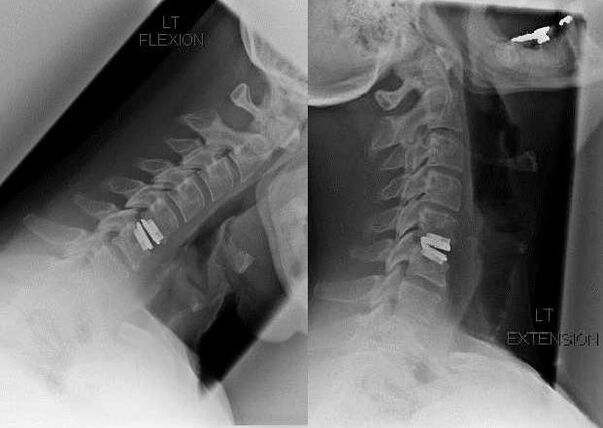

surgical intervention

Indications for surgical intervention include failure of conservative treatment and complications of cervical osteochondrosis, such as discogenic myelopathy, vertebral artery syndrome, and radicular syndrome.In order to decompress the spinal cord, blood vessels, and spinal cord roots, the following procedures are performed:

- laminectomy;

- Laminotomy;

- foraminotomy;

- facet joint resection;

- Discectomy.

During the surgery, bone fragments and ligaments may be removed, and the disc may be completely or partially removed.For small herniated herniations, laser vaporization of the disc core is often performed.

After resection of vertebral structures, stabilization of the spinal motion segments by spinal fusion or installation of bone and dermal autografts is often required.